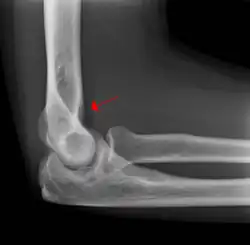

The fat pad sign is invaluable in assessing for the presence of an intra-articular fracture of the elbow. An anterior fat pad is often normal. However a posterior fat pad seen on a lateral x-ray of the elbow is always abnormal. The patient will be unable to flex their elbow and requires orthopaedic input.[2]

Pathophysiology

The posterior fat pad is normally pressed in the olecranon fossa by the triceps tendon, and hence invisible on lateral radiograph of the elbow.[3] When there is a fracture of the distal humerus, or other pathology involving the elbow joint, inflammation develops around the synovial membrane forcing the fat pad out of its normal physiologic resting place. This is visible as the "posterior fat pad sign" and is often the only visible marker of a fracture, particularly in the pediatrics population.